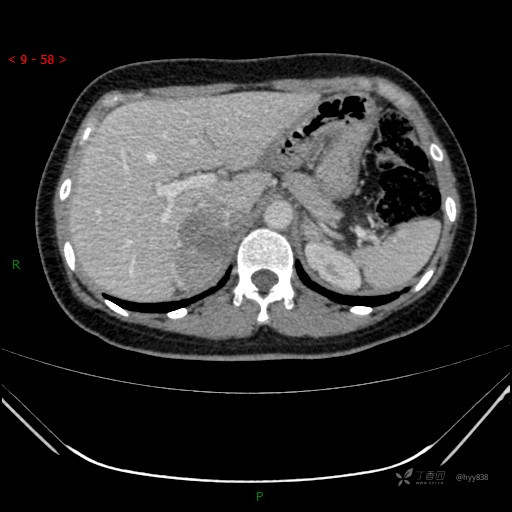

肾上腺CT平扫

动脉期

静脉期